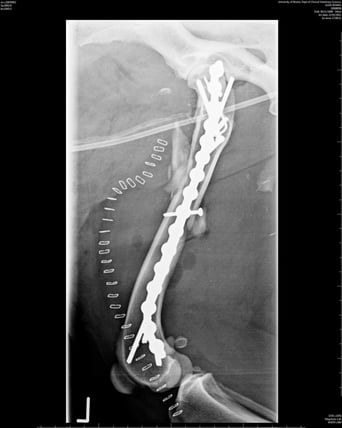

Buttress or bridging

This is when the fracture fragments cannot be aligned. An IM pin is often driven through the furthest ends of the fracture to help align the fragments and then a plate is placed with screws in the proximal and distal parts of the fracture with the main part of the plate acting as a bridge across the gap where the fragments are. This helps to maintain alignment of the limb. Used alone in this way, the plate would be exposed to bending forces which is why it is often used alongside an IM pin as this will counteract these forces. Used in this way, the plate and pin will take on the load, giving the bone time to heal ( Figure 4; Conzemius and Swainson, 1999). The size of the plate and screws used will be determined by the surgeon based on preoperative radiographs. The size of the plate will determine the size of the screws; for example, a 2.0mm plate will always require 2.0mm screws, a 3.5mm plate will require 3.5mm screws, and so on.